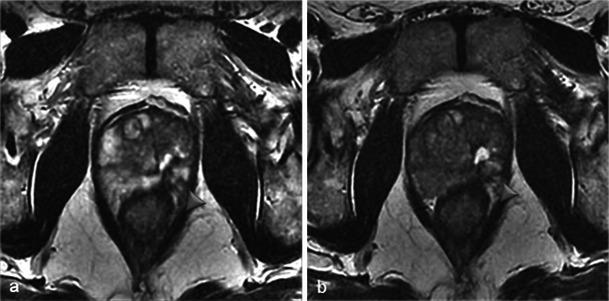

In this technique, a photosensitising agent is introduced intravenously, then activated by local laser illumination to induce tumour necrosis. Treatment efficacy is assessed by magnetic resonance imaging (MRI).

We illustrate specific post-treatment MRI aspects at early and late follow-up with pathological correlations.

• Dynamic phototherapy is a new and promising focal therapy for prostate cancer. • One-week MRI shows increased volume of the treated lobe and large, homogeneous necrosis area. • Six-month MRI shows significant changes of the prostate shape and signal. • Six-month MRI becomes "base line" appearance for further follow-up or monitoring.

在该技术中,将一种光敏剂静脉注射,然后通过局部激光照射激活以诱导肿瘤坏死。通过磁共振成像(MRI)评估治疗效果。

我们阐述了早期和晚期随访时特定的治疗后MRI表现及其与病理的相关性。

• 动态光动力疗法是一种用于前列腺癌的新型且有前景的局部治疗方法。• 一周后的MRI显示治疗叶体积增大以及大片均匀的坏死区域。• 六个月后的MRI显示前列腺形态和信号有显著变化。• 六个月后的MRI成为进一步随访或监测的“基线”表现。